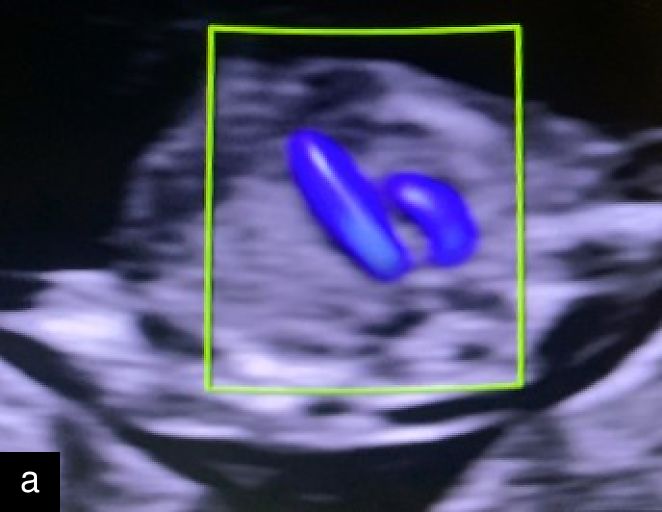

7

(a) Congenital diaphragmatic hernia at 13 weeks with a four-chamber view of the heart (in color) with mediastinal shift and stomach visible in left hemithorax. (b) Congenital diaphragmatic hernia at 20 weeks with a four-chamber view of the heart with the small left ventricle and mediastinal shift, and stomach visible in left hemithorax.